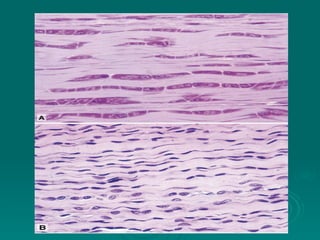

Connective tissues support and bind together other structures throughout the body. They are composed of connective tissue cells, ground substance, and fibers. Connective tissues have few cells separated by an abundant intercellular substance containing fibers. Their main functions are to bind tissues, provide mechanical support, store fat and minerals, allow for metabolite exchange, and aid in repair and healing. Connective tissues are classified as connective tissue proper, which includes loose and dense connective tissues, and specialized connective tissues like cartilage, bone, and blood.